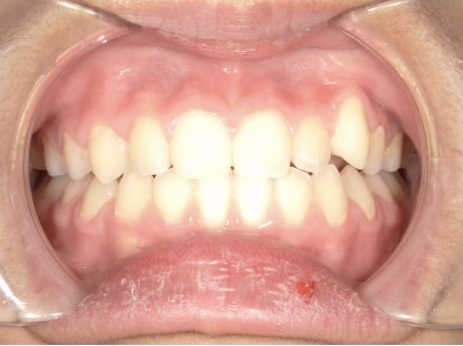

治療中⑦ 中1:12y11m

モノブロック装置継続中、左上八重歯の改善中